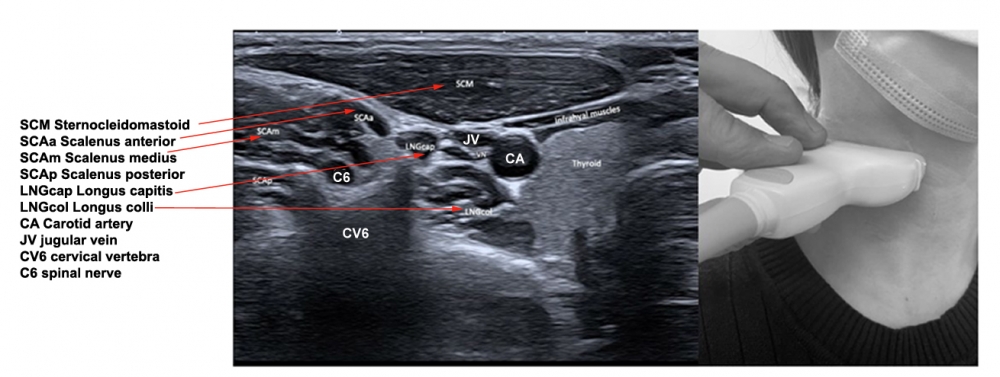

The scalene muscles are identified between the sternocleidomastoid and the levator scapulae. With insertion of the EMG needle into the scalenus muscle, the patient is asked to breathe in as deeply as possible. Since the scalenus is an auxiliary respiratory muscle, EMG activity should be clearly heard on the EMG. Generally either the scalenus posterior or the scalenus medius are treated. Both muscles have the same function: to elevate the rib to which they attach, and to bend and rotate the neck.

Scalenus anterior lies behind the sternocleidomastoid, over the lateral aspect of the neck.

The muscle arises from the anterior tubercles of the transverse processes of C3-C6, and attaches onto the scalene tubercle, on the inner border of the first rib. It is located between the subclavian vein and the subclavian artery. The roots of the brachial plexus pass posterior to it. The phrenic nerve crosses its anterior surface.

Scalenus medius is the largest muscle of the scalenus group, and arises from the transverse processes of the cervical vertebrae and inserts into the superior portion of the first rib. This muscle can elevate the first rib or bend and rotate the neck. A needle can be placed into the scalenus medius muscle by palpating the belly of the muscle, in the floor of the posterior triangle, two finger breadths anterior to the anterior border of the trapezius muscle. At this point the muscle is just beneath the skin. The upper portion can be inserted by placing the needle just anterior to the lateral edge of the splenius capitis muscle to a depth of 1.5 to 3.0 cm.

Scalenus posterior arises from the posterior portion of the transverse processes of C5–6, passing medially and posteriorly to the scalenus medius, and inserts into the outer surface of the second rib, deep to the attachment of the serratus anterior. The scalenus posterior elevates the second rib or bends and slightly rotates the neck.

Figure 7. Trajectory of approach and relationships of the surrounding muscles to scalenus